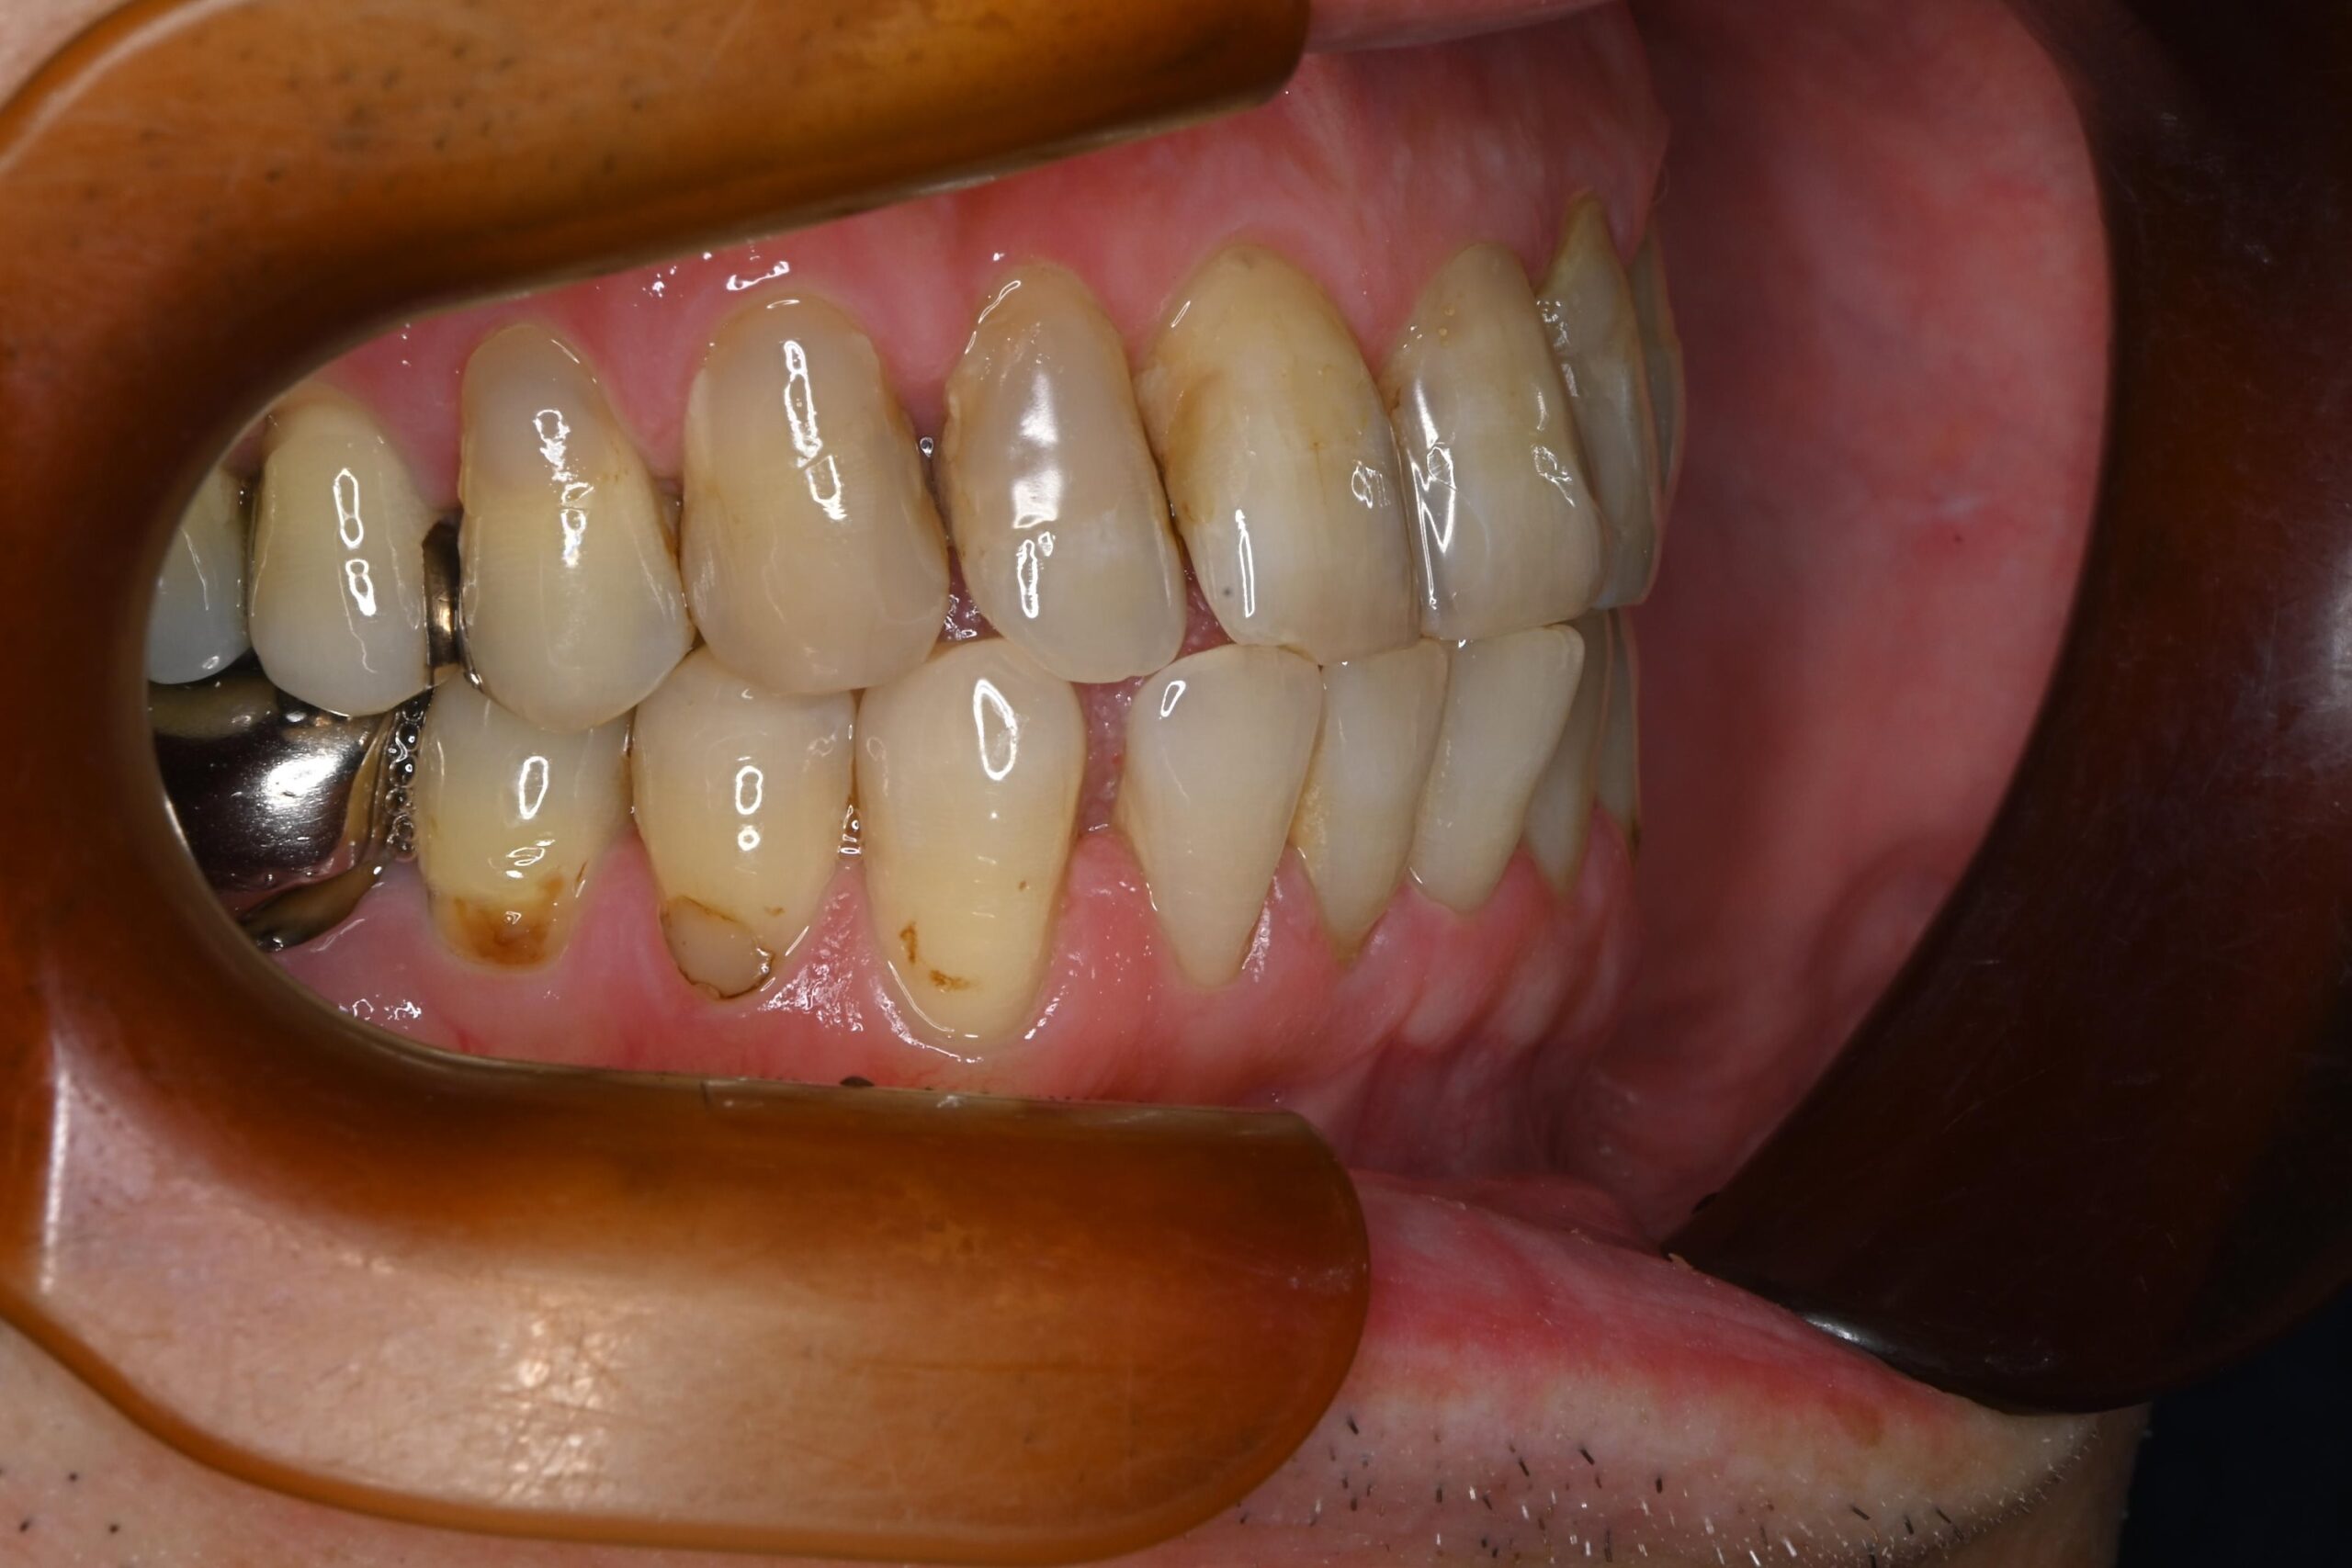

初診時の口腔内の状態:

お口全体に虫歯や歯周病の原因となるプラーク(歯垢)が多く付着していました。右上奥歯は重度の虫歯で歯冠部(歯の頭)が失われており、左下奥歯は過去の治療箇所から細菌が入り込み、根の先に炎症が起きている状態でした。

また、左右の奥歯にはWSD(楔状欠損)があり、知覚過敏も見られました。

Before